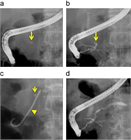

1. 膵管内の結石(膵石)を認めた場合と、膵全体に分布する複数かつびまん性の石灰化を認めた場合は慢性膵炎と診断できる(推奨度1)